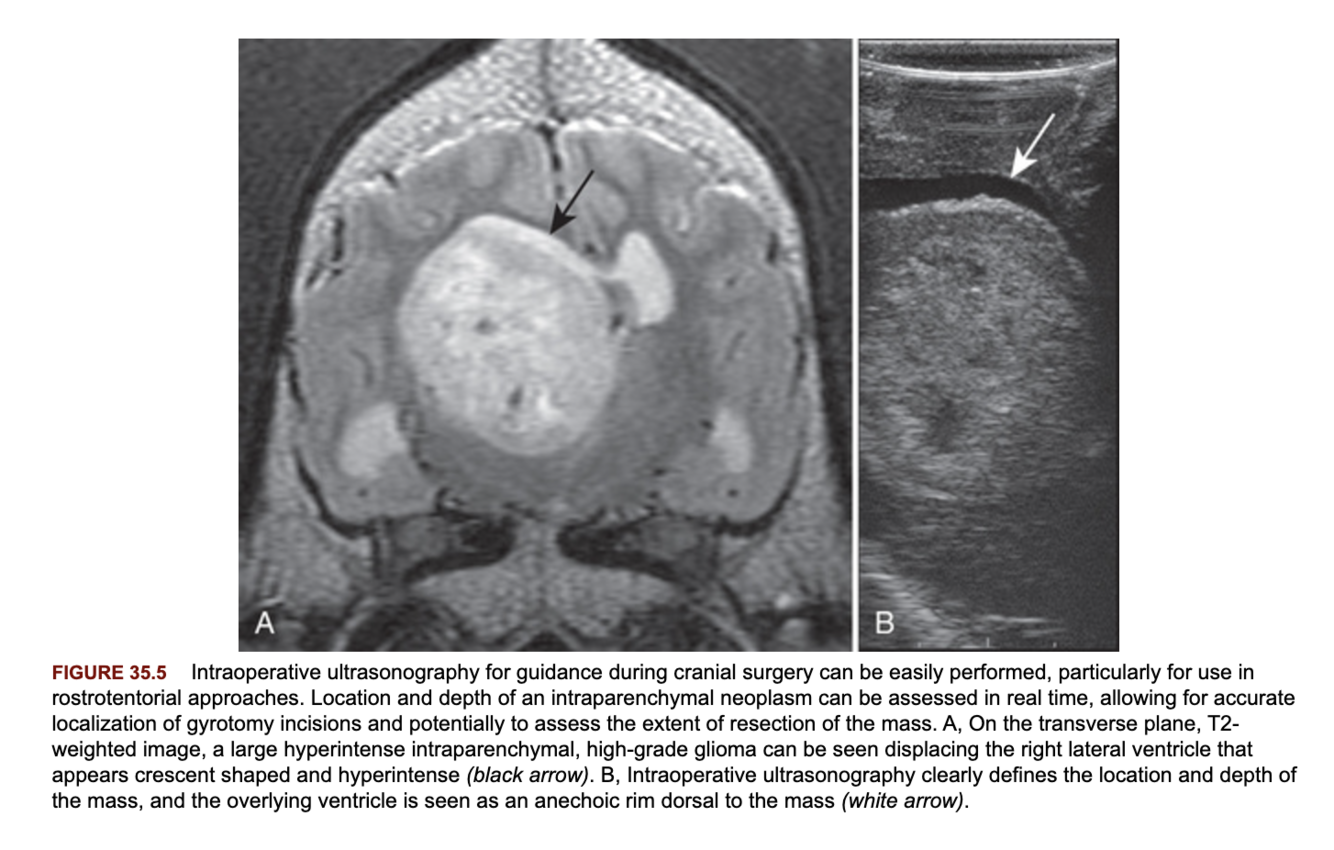

1. Intraoperative neuronavigation based off pre-operative MRI (may be limited by brain shift and alterations in structure after the surgery is started).

2. Intraoperative MRI.

3. Intraoperative ultrasound.